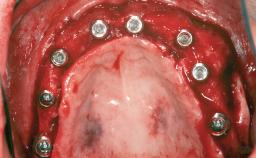

# of Teeth 4

# of Implants 4

Type of Implants One-Piece|Two-Piece

Guided Surgery Yes